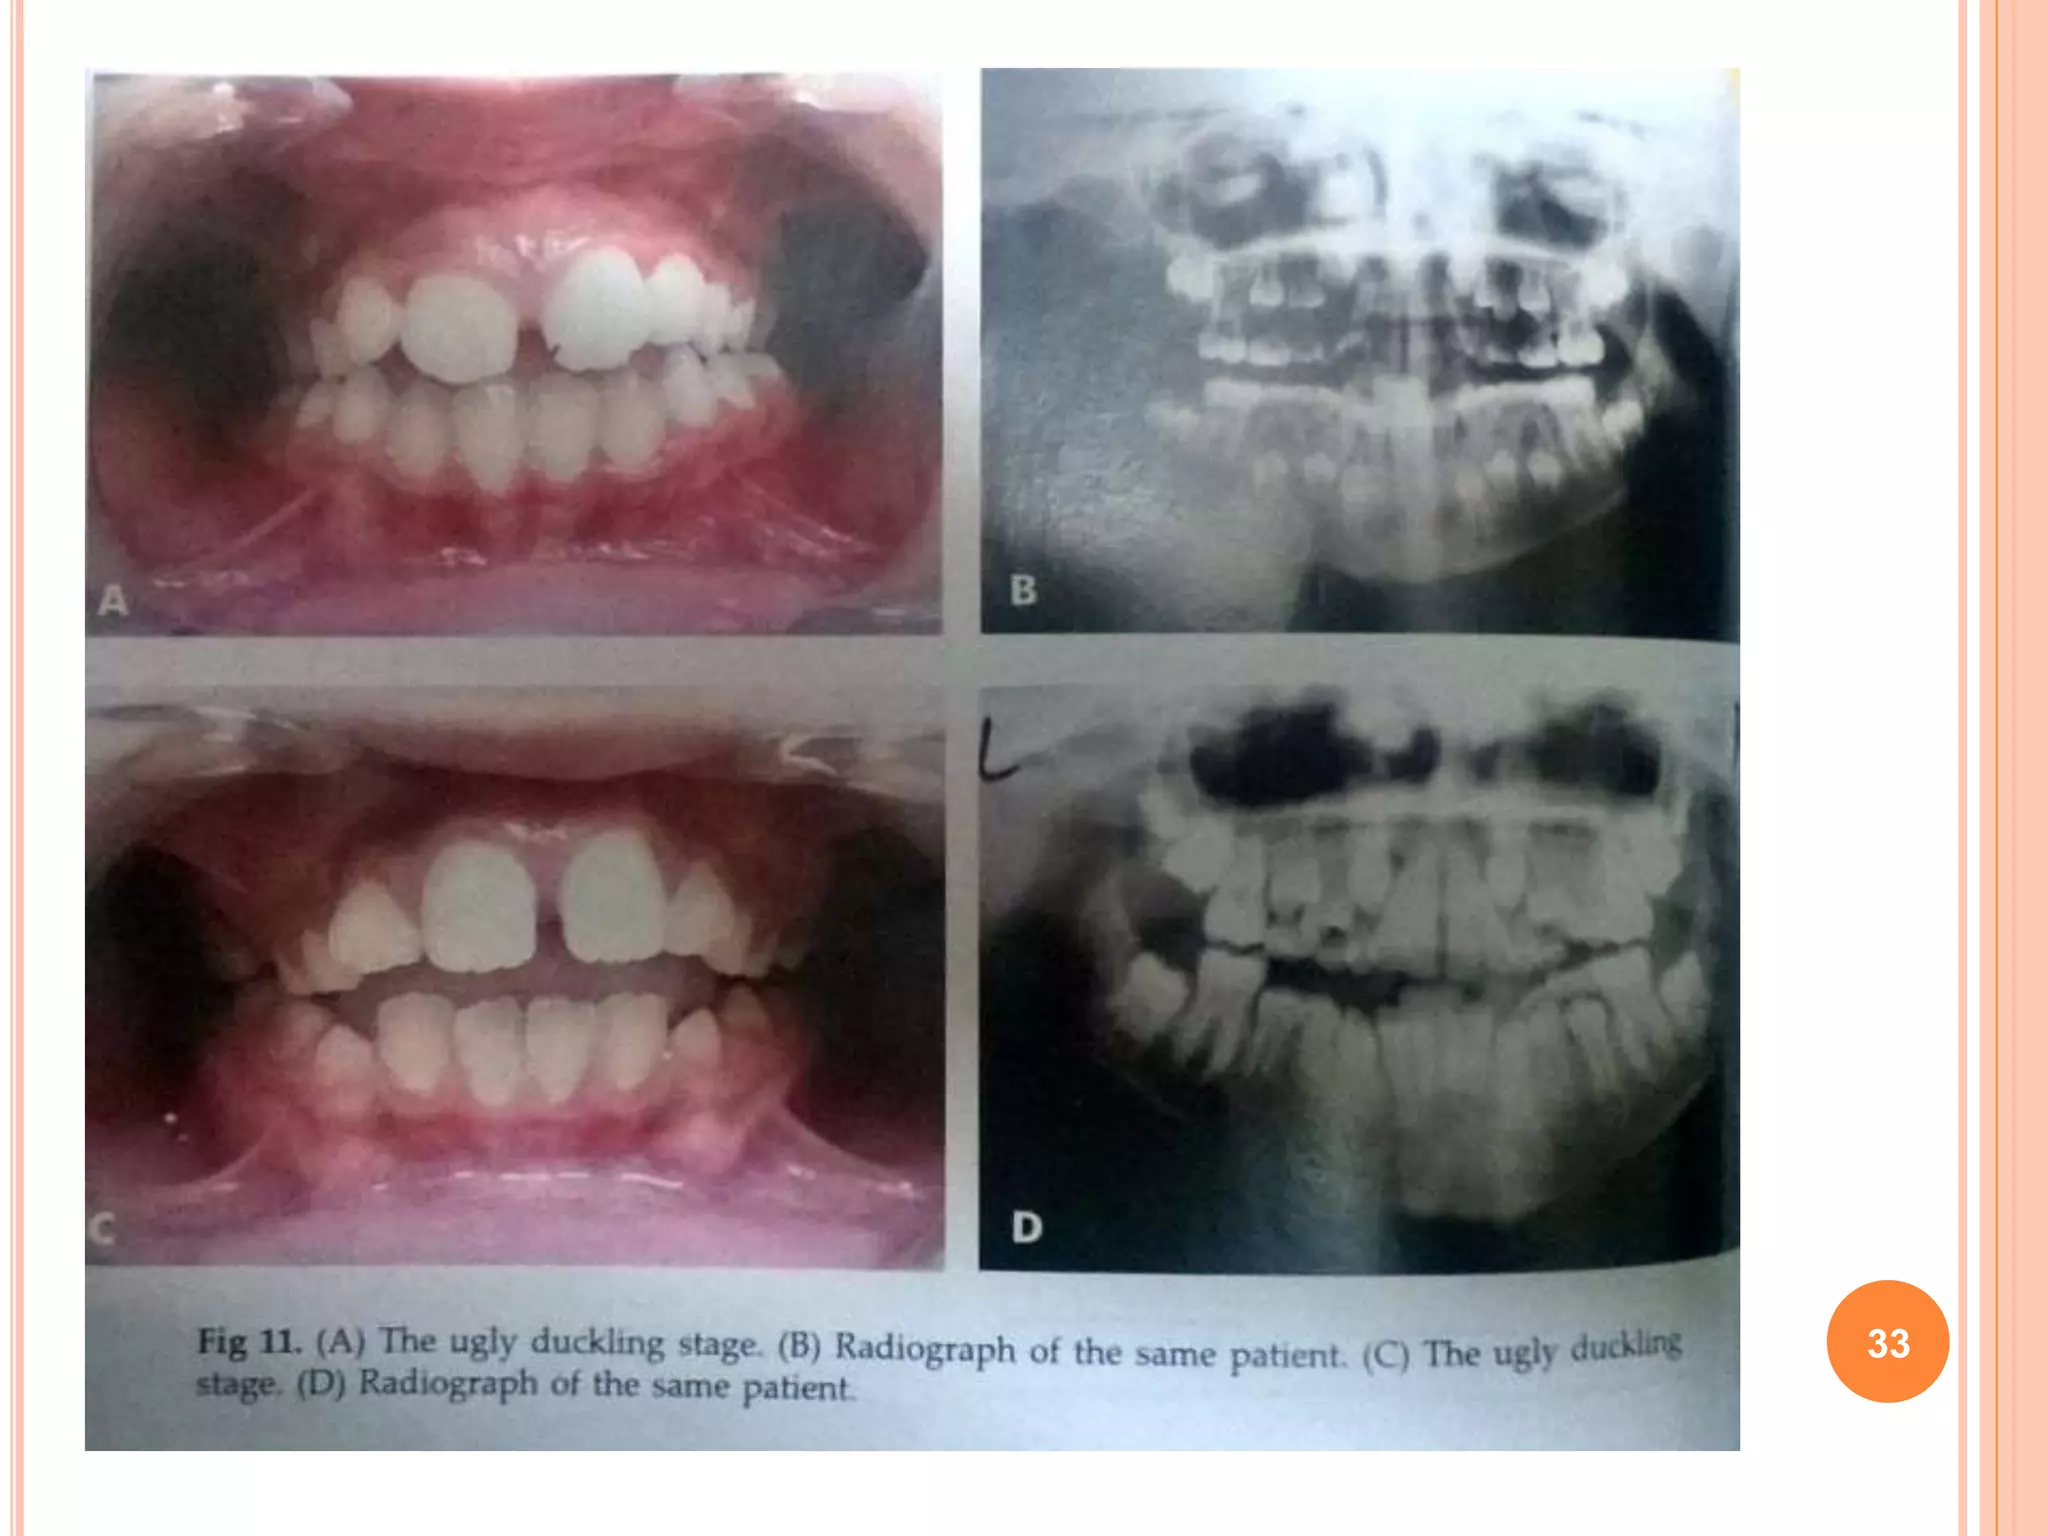

UGLY DUCKLING STAGE

 Sometimes a transient self-correcting

malocclusion is seen in the maxillary incisor

region between 8 to 9 years of age.

 This is a particular situation seen during the

eruption of the permanent canines.

 As the developing permanent canines erupt

they displace the roots of the lateral incisors

mesially. This results in transmitting the force

on to the roots of the central incisors, which

also get displaced mesially.

 A resultant distal divergence of the crowns of

the two central incisors causes a midline

spacing. This situation has been described by

Broadbent as the ugly duckling stage.

 This condition usually corrects by itself when

the canines erupt and the pressure is

transferred from the roots to the coronal area

of the incisors.

32

33